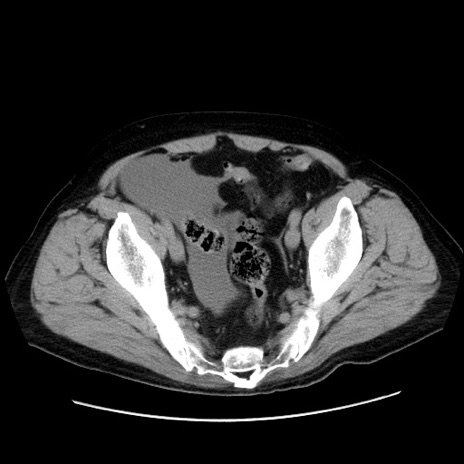

冠状断像

症例30(横断像)

【症例】80歳代男性

【現病歴】約6時間前から臍下部痛が出現。次第に腹部膨隆・背部痛も生じてきたため来院。背部痛の場所は変化しない。

【身体所見】意識清明、BT 36.3℃、BP  131/87mmHg、P 87bpm、SpO2 100%(RA)、臍周囲自発痛・圧痛あり、反跳痛なし、自発痛部位に一致して板状硬あり、腹部膨隆、腸雑音減弱、CVA tenderness両側陰性。